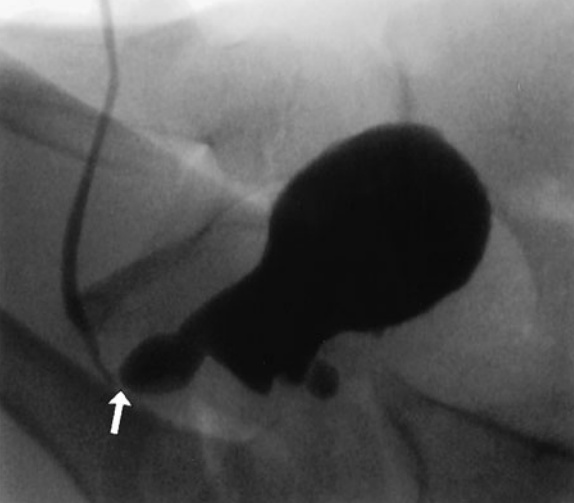

Physical examination of a baby boy shortly after birth reveals a large bladder and palpable kidneys. The nurses note that he produces a weak urinary stream. A voiding cystourethrogram is shown below. He appears to be otherwise normal. Which of the following is the most likely diagnosis?

b. posterior urethral valve